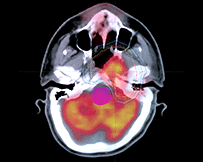

影像引導(dǎo)放射治療(IGRT)

IGRT是一種四維放射治療技術(shù),它在三維放療技術(shù)的基礎(chǔ)上加入了時(shí)間因數(shù)的概念,充分考慮了解剖組織在治療過程中的運(yùn)動(dòng)和分次治療間的位移誤差,在患者進(jìn)行治療過程中利用影像設(shè)備對(duì)腫瘤及正常器官進(jìn)行實(shí)時(shí)監(jiān)控,并根據(jù)器官位置的變化調(diào)整治療條件,使照射野緊緊“追隨”靶區(qū),使之能做到真正意義上的精確治療。